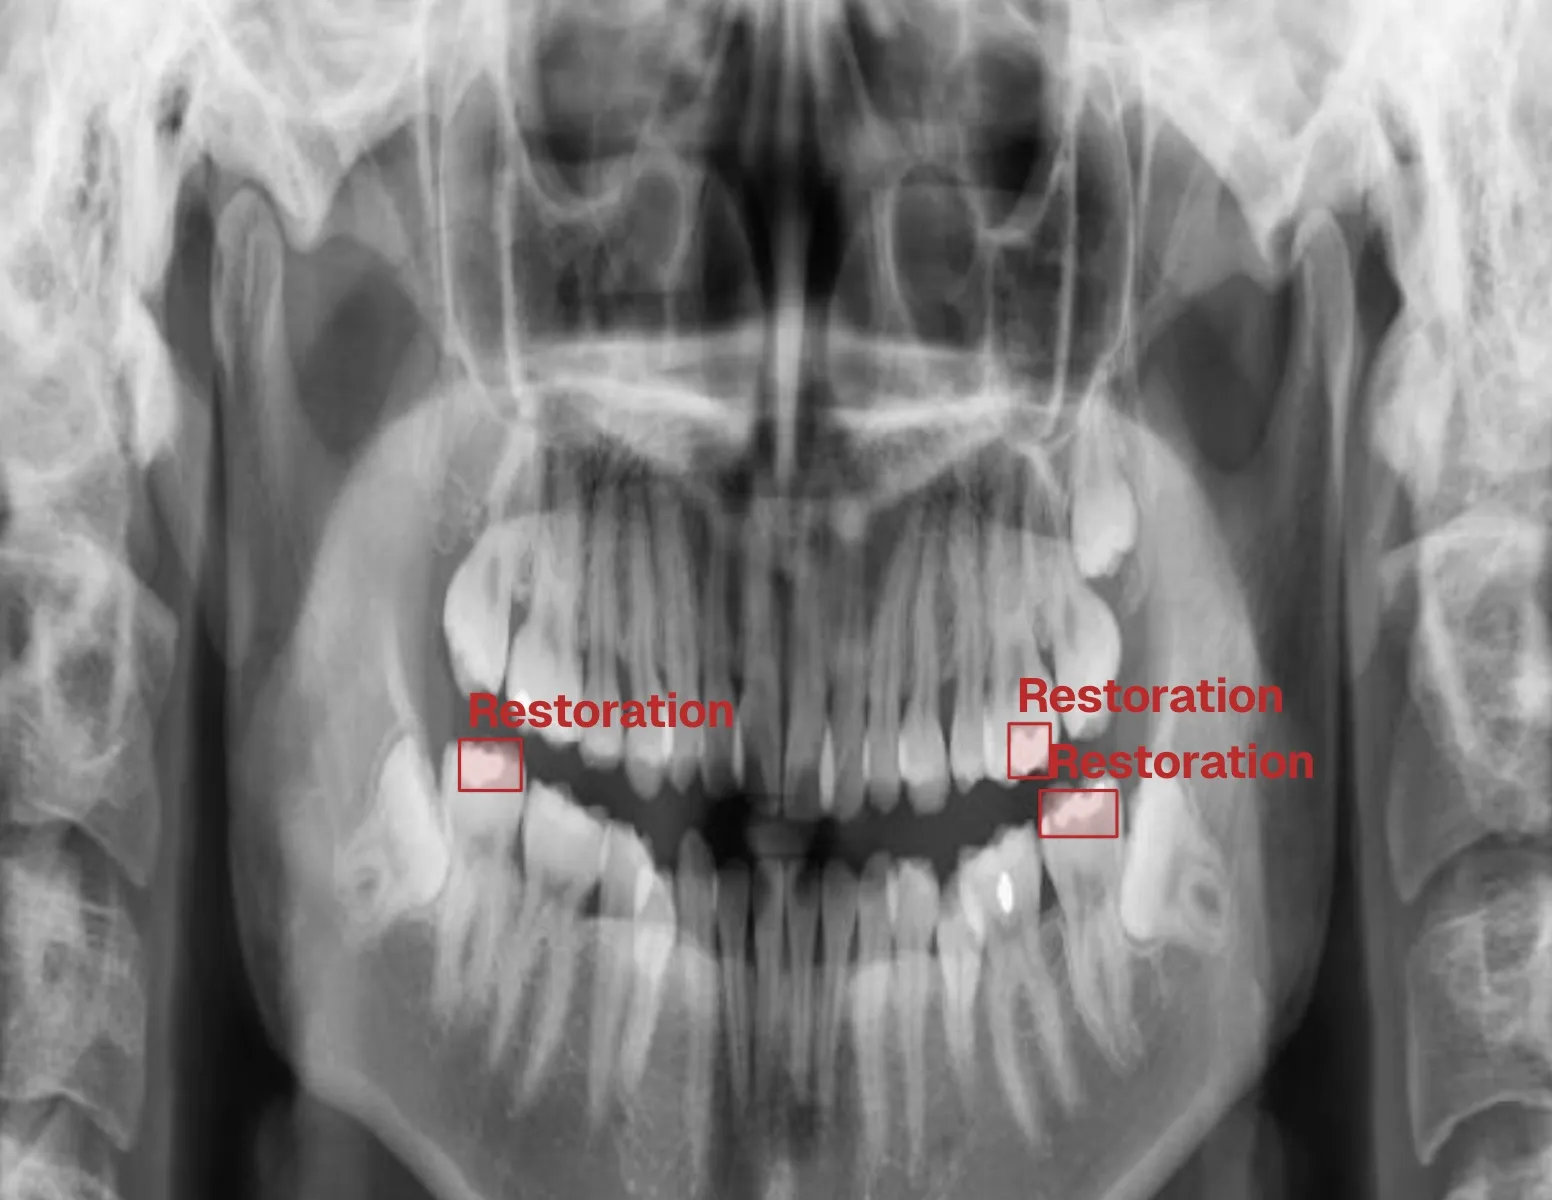

Restorative Care

Fillings, crowns, bridges, and full-mouth rehabilitation for optimal function.